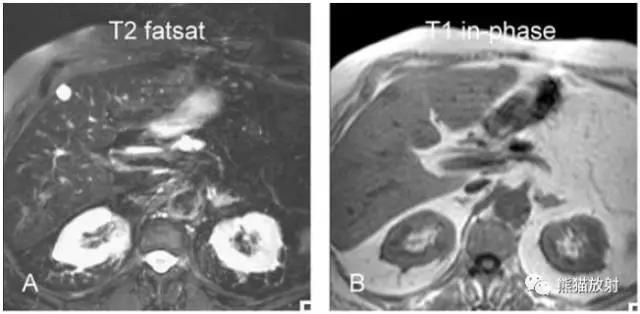

各序列信号特征:

T2 fatsat:T2压脂,血管瘤呈多发高信号;肝、脾由于铁沉积呈低信号;

T1 in-phase:T1同相位,低信号;脾脏由于铁沉积呈明显低信号;

肝脏多发血管瘤

结肠癌患者,发现肝脏病变,怀疑转移。

图A、B:超声发现肝内多发异常回声,左叶大者回声不均;

图C、D:动脉期两个病灶边缘结节样强化,延迟期左叶较大病灶持续强化。